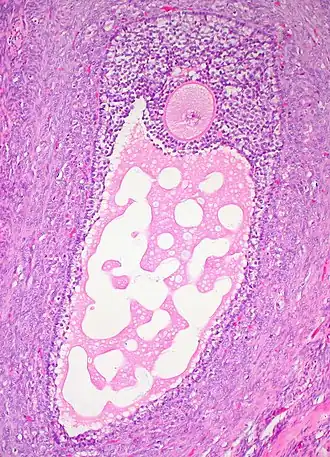

![]() Гистологический срез зрелого фолликула яичника. Ооцит — большая, круглая, розово окрашенная клетка в верхней части изображения. | |

В фолликуле содержится ооцит 1-го порядка. Ядро ооцита называют «зародышевый пузырёк» germinal vesicle (см. иллюстрацию)

Ооцит окружён слоем гликопротеинов, zona pellucida (zona striata). Он, в свою очередь, окружён слоем гранулёзных клеток.

Гранулёзные клетки окружены тонким слоем внеклеточного матрикса — базальной мембраной (на рисунке обозначена, как fibro-vascular coat). Вокруг базальной мембраны находятся тека-клетки.